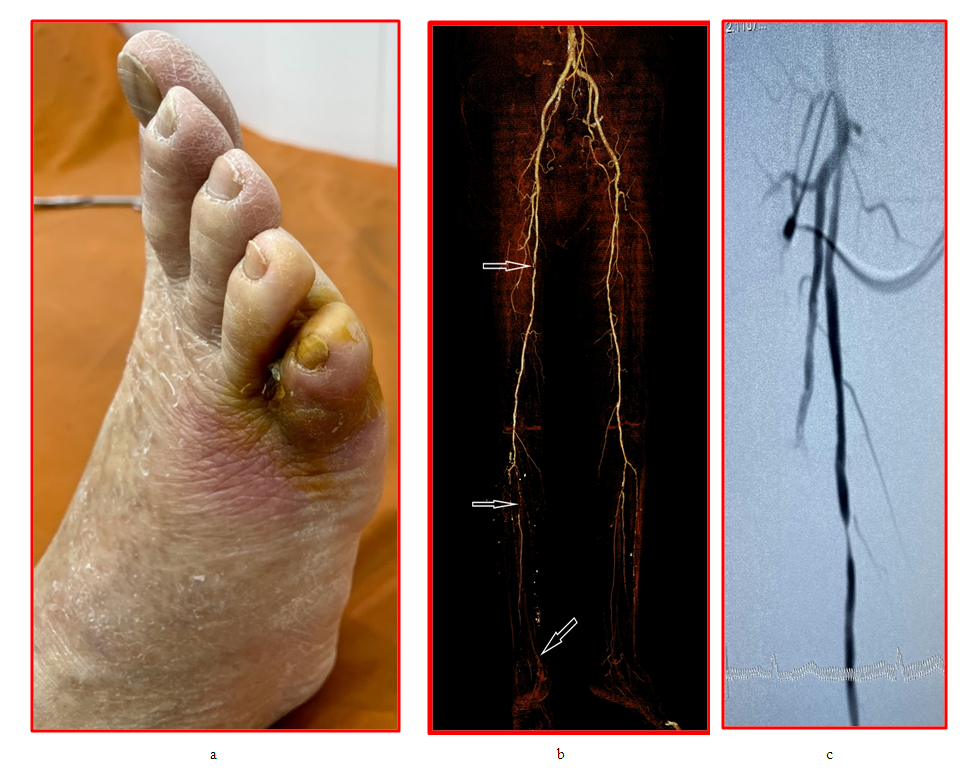

| Figure 3. a) - Gangrene of the right fifth toe, b) CT angiography - focal occlusion of the SFA (arrow), focal occlusion and stenosis of the tibioperoneal trunk and PA (arrow), extended occlusion of the ATA and PTA, the dorsal artery of the foot is contrasted through the collateral arteries plantar arteries (arrow), c) digital subtraction angiography - focal subocclusion of the SFA |